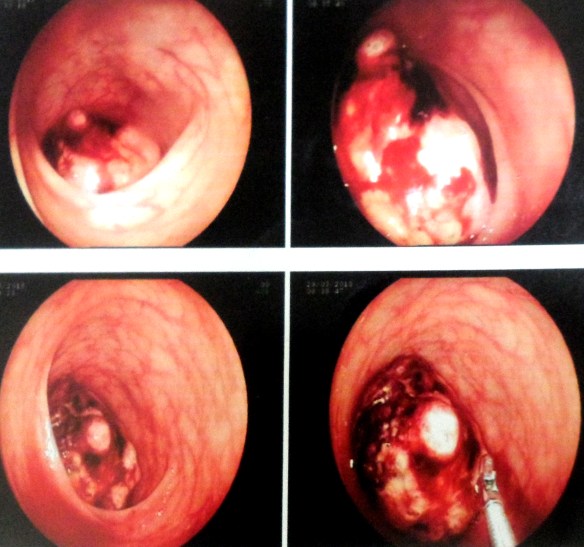

On 29 May 2018, CHK went back to the hospital again for a colonoscopy. There was a tumour in his colon and 85 percent of the passageway was blocked. A biopsy confirmed adenocarcinoma of the ascending colon.